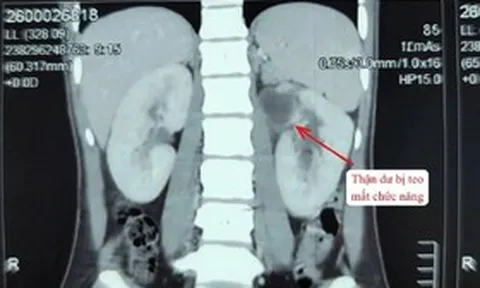

Từng là gương mặt quen thuộc của sân khấu và màn ảnh phía Bắc, Hoàng Cúc trải qua một biến cố lớn khi mắc bệnh ung thư. Có những thời điểm, bệnh tình khiến bà suy kiệt, tưởng như không thể vượt qua. Nhưng chính trong những khoảnh khắc mong manh ấy, nữ nghệ sĩ lại tìm ra một triết lý sống giản dị "còn sống ngày nào, hãy vui ngày đó".